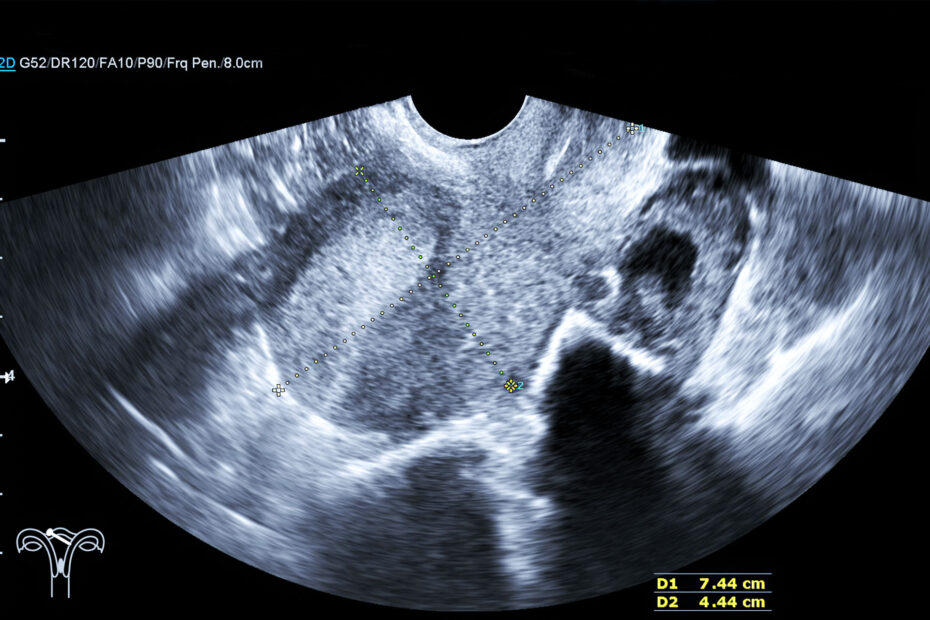

Ecografia endocavitaria: indicazioni cliniche, modalità di esecuzione e vantaggi diagnostici

L’ecografia endocavitaria è una tecnica di imaging ecografico che prevede l’introduzione di una sonda all’interno di una cavità corporea, naturale, al fine di ottenere immagini ad alta risoluzione di organi e strutture anatomiche non facilmente valutabili con approccio transcutaneo.

- ecografia transvaginale, utilizzata per lo studio dell’utero, delle ovaie, dell’endometrio e in generale della pelvi. È la metodica di riferimento in ginecologia per valutazioni di infertilità, dolore pelvico, sanguinamenti anomali, cisti ovariche e tumori ginecologici;

L’impiego di sonde ad alta frequenza consente una risoluzione eccellente delle immagini, pur con una profondità di campo limitata, motivo per cui la metodica è indicata soprattutto per strutture pelviche o profondamente localizzate.

Durante l’esame è possibile eseguire misurazioni precise, valutare flussi vascolari con Doppler o prelevare campioni bioptici in modo mirato, se necessario.